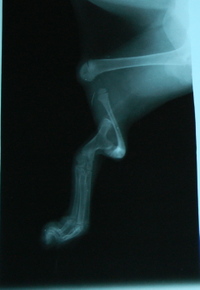

Tibbys_xray_2

Here is the X-ray of Tibby’s leg. You can see how radically different it is.  Not only is there no fibula, but the tibia — which is supposed to be long and straight and thick — is short and twisted and circles completely around.  It also doesn’t connect at all with the femur, which is why their legs dangle and flop when we hold the kittens up in the air.

Weird, huh?  So weird that our internal medicine specialist at the clinic, Dr. Britt Culver, has never seen anything like this before, and nor has Jennifer.